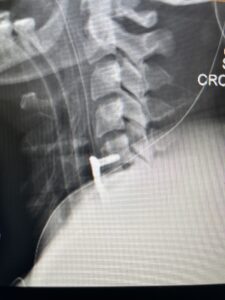

This 47-year-old male who four months prior was lifting weights developed sharp pain in his neck. After that he developed progressive numbness in his arms, neck pain and headache. He said that the right arm was worse than the left. On examination the patient had long tract weakness on the right side which included his triceps, finger extensors, hip flexors, and dorsiflexors. The patient did not have hyperreflexia. MRI (Fig. 2) demonstrated a massive, extruded disc herniation with severe cord compression. The patient because of progressive myelopathy and spinal cord compression was indicated for anterior cervical discectomy and fusion at C4-5 (Fig. 3). Patient had significant improvement of weakness and numbness post operatively.

Fig. 3 Intraoperative lateral cervical X-Ray demonstrating C4-5 ACDF